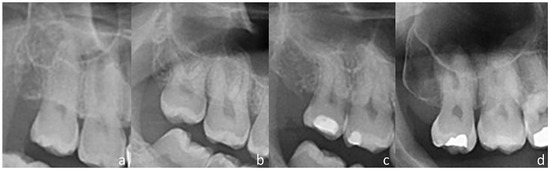

2.2. Image Acquisition and Evaluation